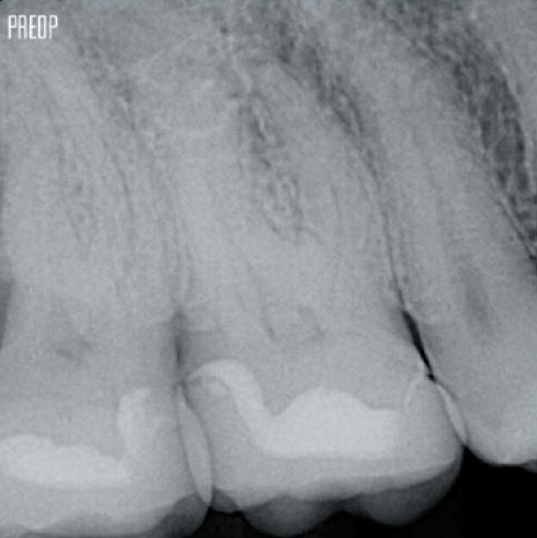

Successful root canal treatment starts with adequate access to the pulp chamber. The ideal procedure provides access to root canal orifices with minimal loss of dentin.

A Conservative Endodontic Cavity (CEC) is the recommended with the TruNatomy® system.

Access is now possible from different angles while until now, structure needed to be sacrificed (traditional endodontic cavity).1

No need for straight line access.1

More dentin preserved. Appropiate shaping, irrigation, and obturation ensured.

Photos courtesy of Dr. Ahmed Salman